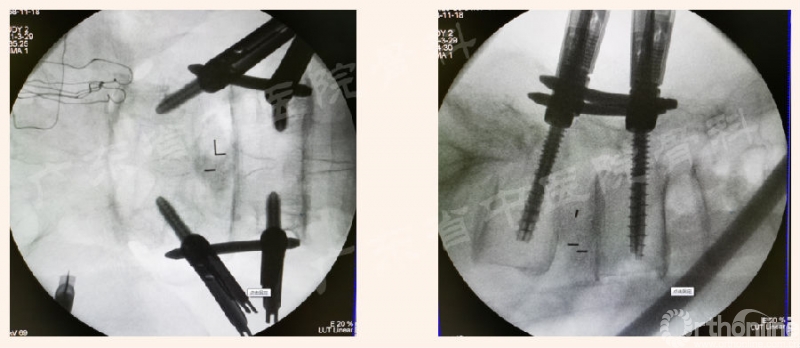

为进一步解决临床实际问题,本期内容将针对腰椎Endo-PTLIF的标准化流程,按照手术常规步骤中椎管外、进入椎管、椎管内的操作进行介绍,详见下文。

2. 椎板切除术

第3半管:半齿环锯-上关节突(尖及内侧)

骨凿OR枪咬上关节突

10. Cage置入:活动页片